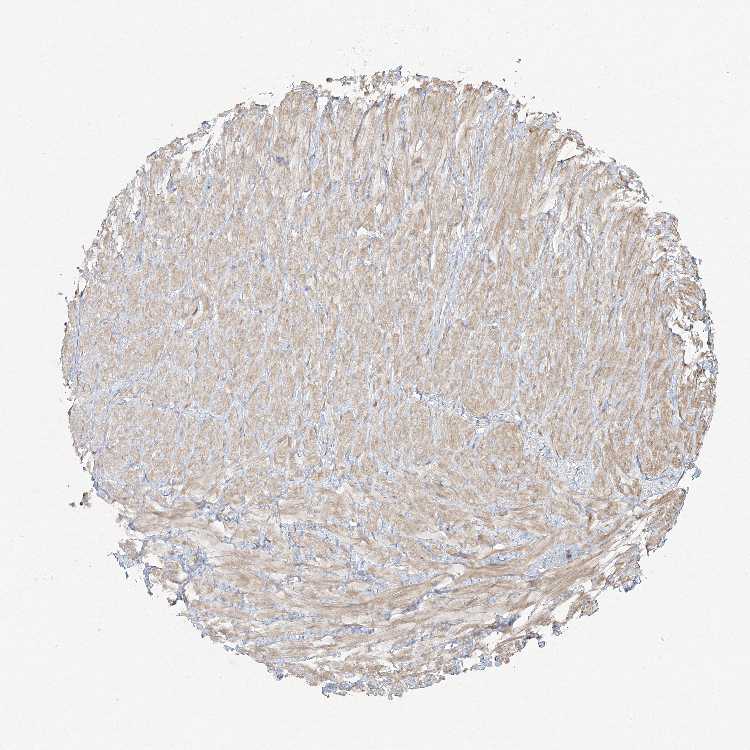

SOFT TISSUE 1 - Antibody stainingi

Antibody staining in the annotated cell types in the current human tissue is reported as not detected, low, medium, or high, based on conventional immunohistochemistry profiling in selected tissues. This score is based on the combination of the staining intensity and fraction of stained cells.

Each image is clickable and will lead to virtual microscopy that enables deeper exploration of all samples and also displays staining intensity scores, fraction scores and subcellular localization as well as patient and tissue information for each sample.

Antibody HPA036342Antibody HPA036343

Chondrocytes Not detected-

Fibroblasts LowNot detected

Peripheral nerve Not detected-

SOFT TISSUE 2 - Antibody stainingi

Antibody HPA036342

Chondrocytes Low

Fibroblasts Low

Peripheral nerve Not detected